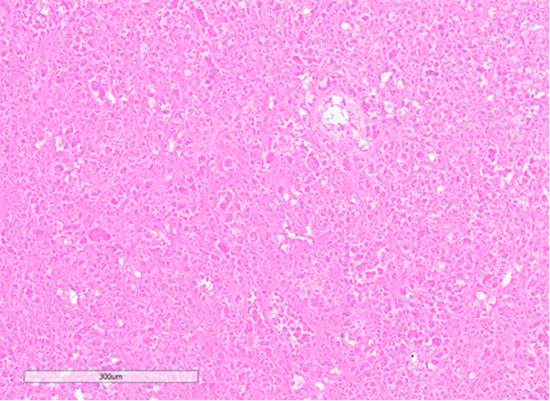

Figure 7: Section showing areas of tumor cell necrosis (Hematoxylin and Eosin stained (10x)